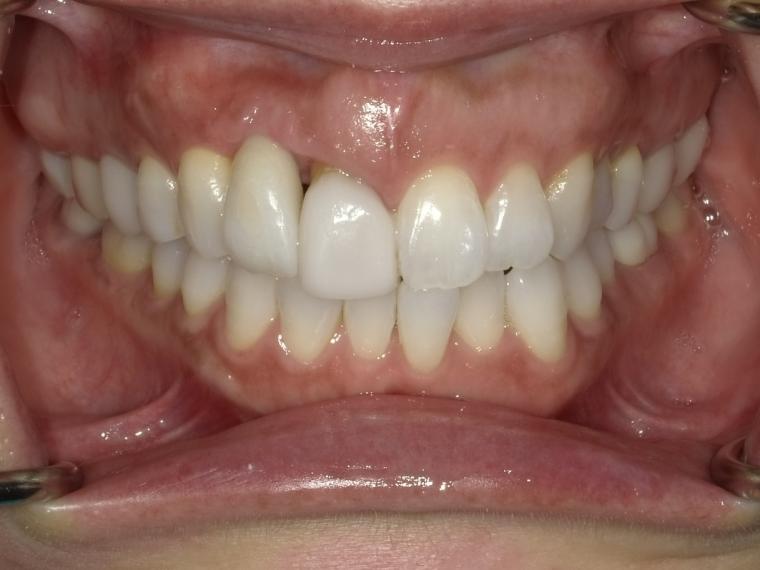

AFTER

53歳女性/上1本欠損/インプラント埋込手術

前歯の詰め物が割れたかもしれないの主訴でご来院された方です。

保存状態が厳しかった為、上顎側切歯の抜歯となりました。

抜歯後に土台となる骨を作る処置の後、インプラントを1本埋入しました。